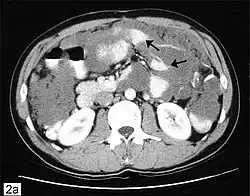

Badaniem obrazowym wskazanym w diagnostyce PMP jest tomografia komputerowa. Niezbędna jest biopsja i badanie histopatologiczne.